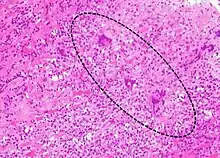

A microscope image of myocarditis at autopsy in a person with acute onset of heart failure

Lymphocytic myocarditis (white arrow points to a lymphocyte), commonly showing myocyte necrosis (black arrow), seen as hypereosinophilic cytoplasm with loss of striations.